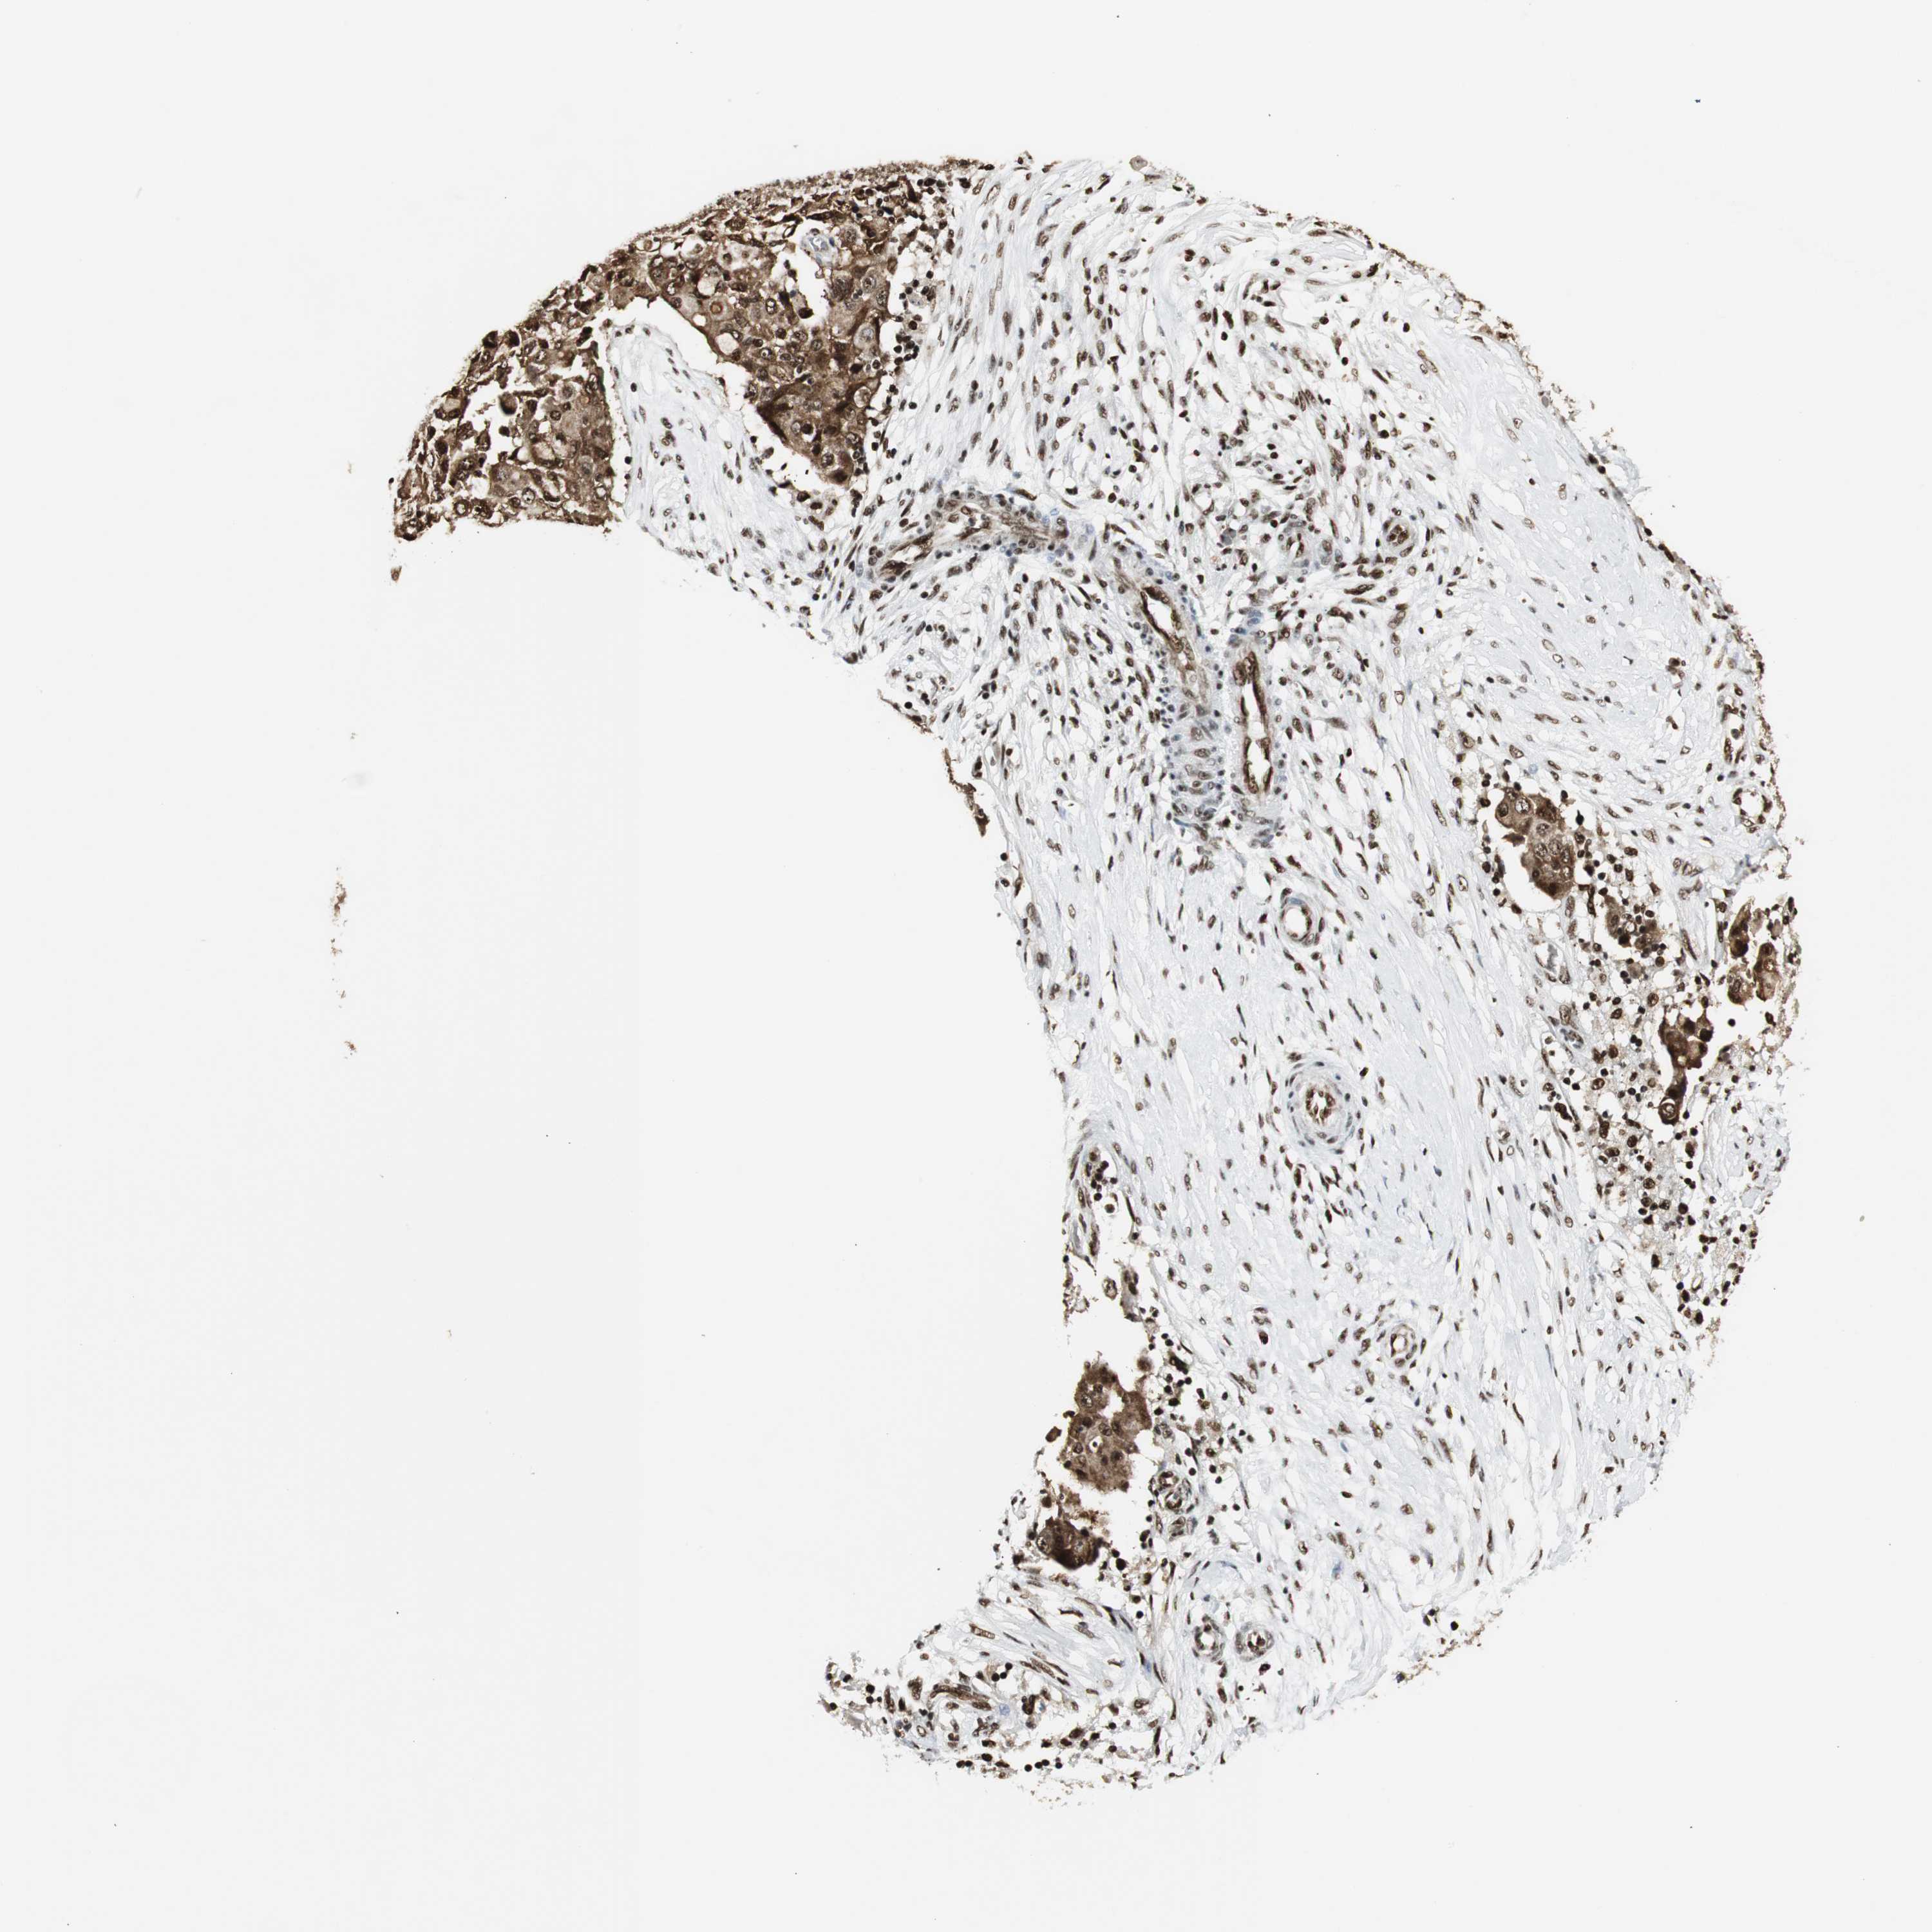

OVARIAN CANCER - Protein expressioni

A mouse-over function shows sample information and annotation data. Click on an image to view it in a full screen mode. Samples can be filtered based on level of antibody staining by selecting one or several of the following categories: high, medium, low and not detected. The assay and annotation is described here.

Note that samples used for immunohistochemistry by the Human Protein Atlas do not correspond to samples in the TCGA dataset.

Antibody stainingi

Antibody staining in the annotated cell types in the current human tissue is reported as not detected, low, medium, or high, based on conventional immunohistochemistry profiling in selected tissues. This score is based on the combination of the staining intensity and fraction of stained cells.

Each image is clickable and will lead to virtual microscopy that enables deeper exploration of all samples and also displays staining intensity scores, fraction scores and subcellular localization as well as patient and tissue information for each sample.

Antibody HPA006314

Antibody HPA012010

Antibody CAB011673

Cystadenocarcinoma, serous, NOS

Carcinoma, endometroid

Carcinoma, NOS

Cystadenocarcinoma, mucinous, NOS